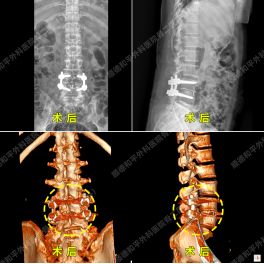

案例三:微创联合康复——中年患者的长期症状缓解51岁梁小波,10年前无明显诱因出现腰痛,反复发作且间断保守治疗无效。近期症状加重,伴左下肢疼痛、麻木,影像学检查诊断为L4/5、L5/S1腰椎间盘突出伴椎管狭窄。

骨二区团队结合患者年龄及病情,制定精准手术方案,术后辅以系统性康复训练(如腰背肌锻炼、半桥训练、飞燕式等)。患者住院治疗期间症状逐日改善,出院后通过持续康复锻炼,有效预防复发,生活质量显著提升。

综合策略:针对中老年患者,术中精准减轻神经压迫,重新稳定腰椎,确保长期疗效,结合术后康复训练,进一步增强腰背肌力量与脊柱稳定性,双管齐下避免复发,体现“治疗-康复”一体化理念。